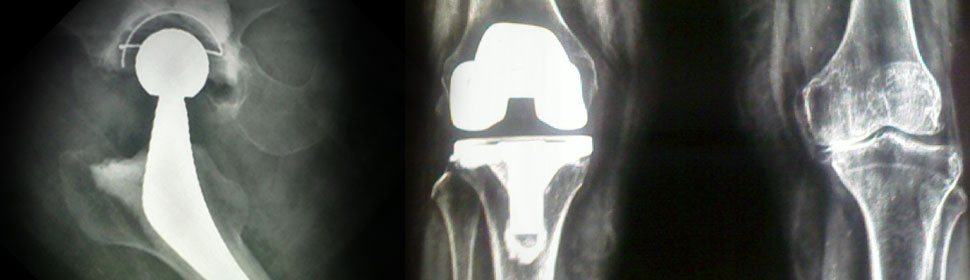

Knee replacement surgery , revisions Hip replacement surgery, bipolar hip, total hip replacements

Hip Replacement Surgery

- Cemented, Cementless, Hybrid, Metal On Metal, Ceramic On Ceramic, Total Hip Replacement

- Hip Resurfacing

- Bipolar Hip Replacement

Knee Replacement Suregery

- Fixed Bearing, Rotating Platform, All –Poly Posterior Stabilised, Hinged Knee Replacement

- Revision Joint Surgery

- Correction Of Very Severe Deformities